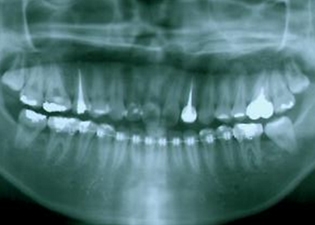

dot  扶正大臼齒

案例